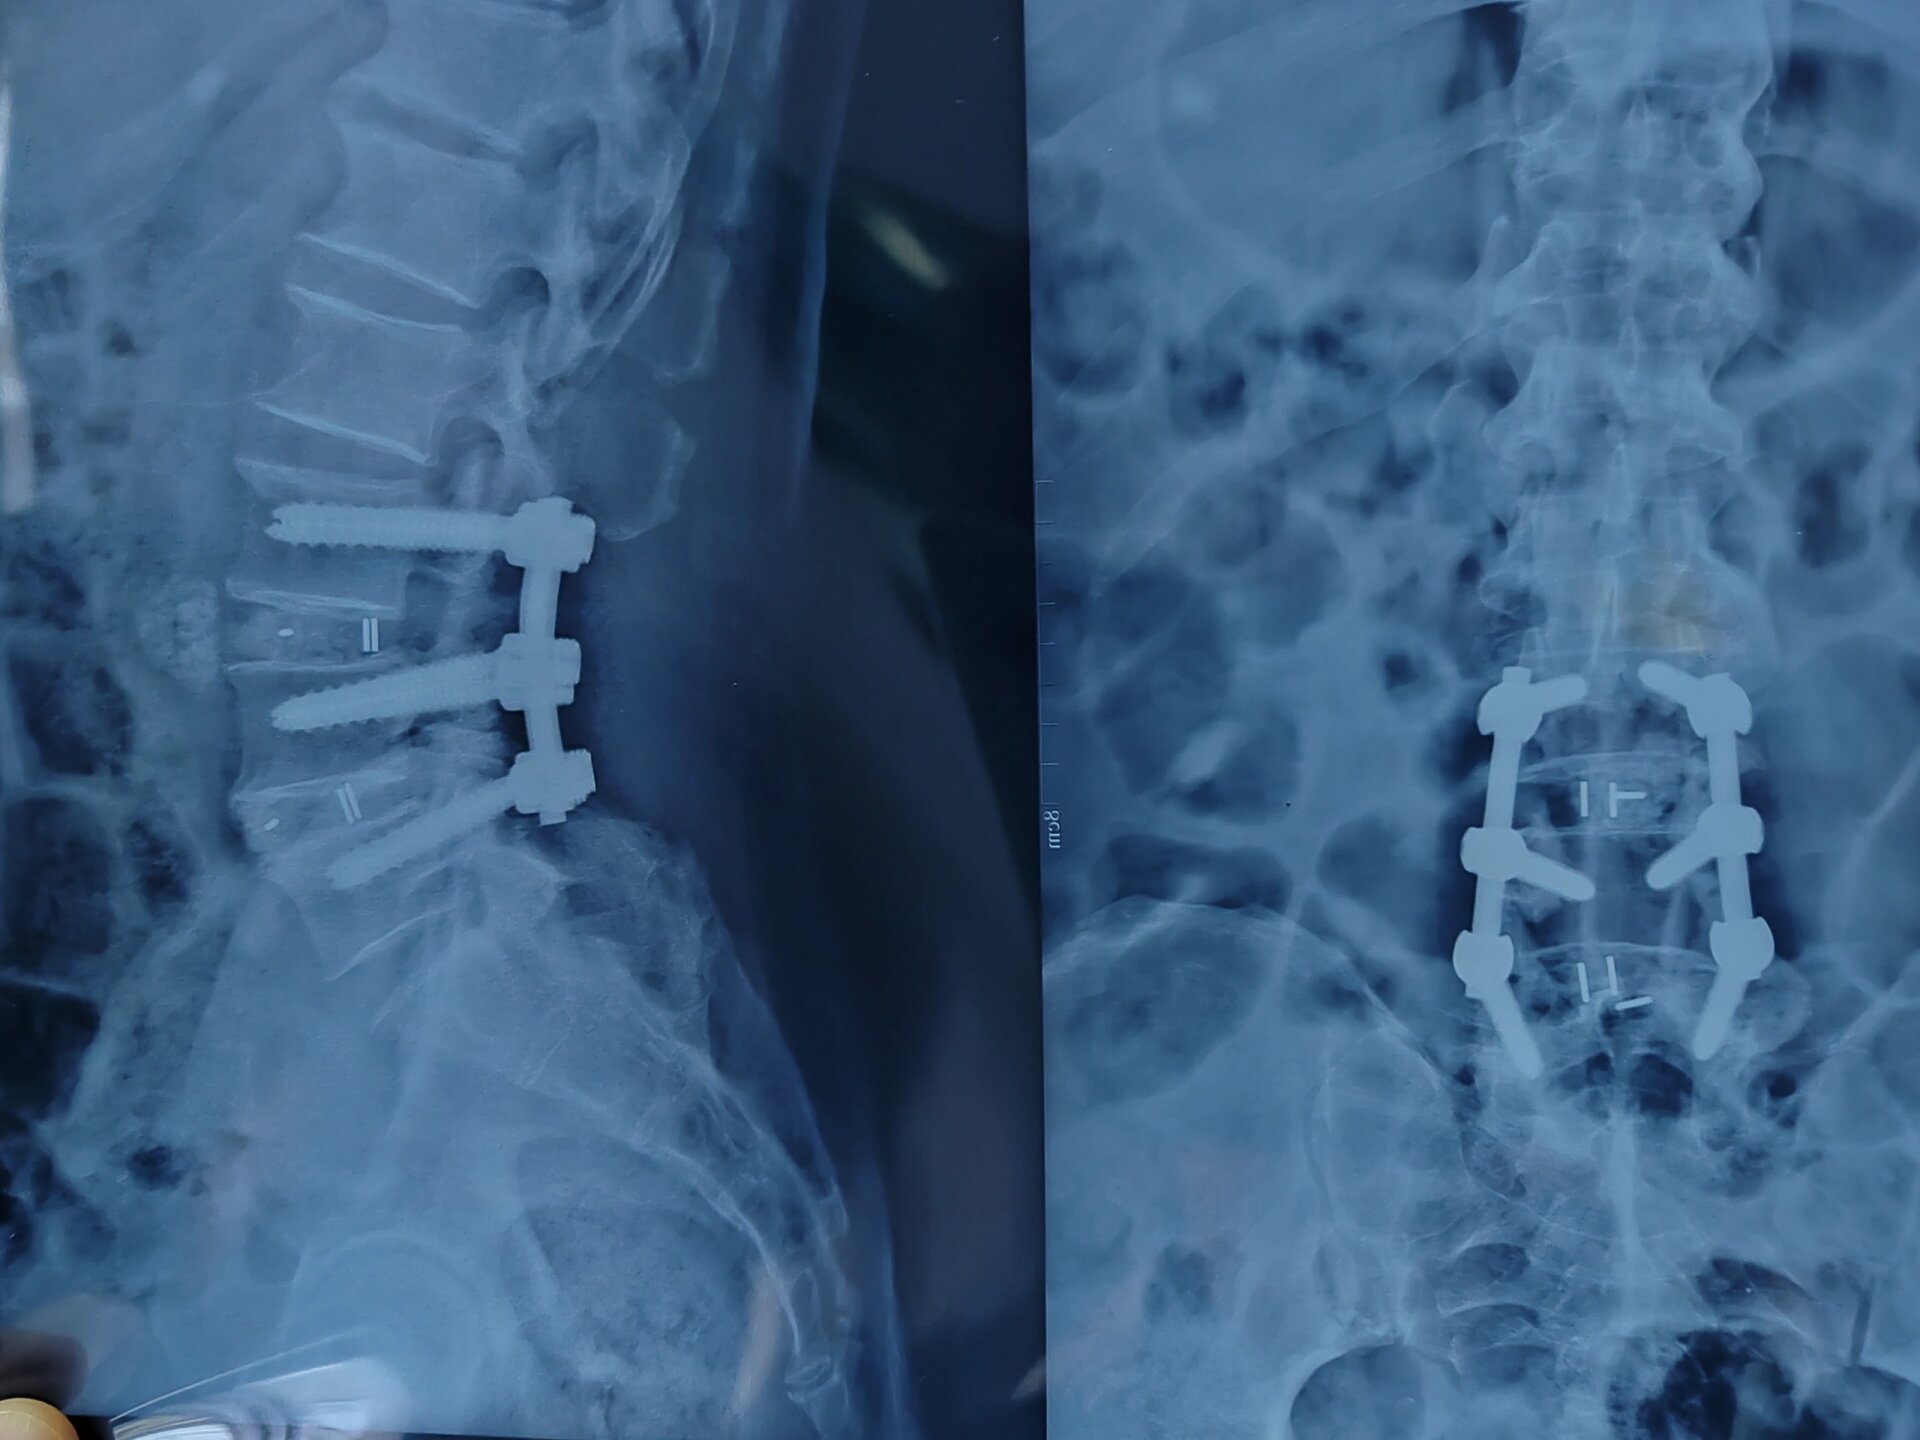

医学影像 原来腰椎钢钉是这样连接的

腰椎开放融合术6个钢钉